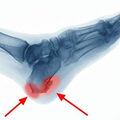

A csípőízületi fájdalmak hátterében számos ok állhat. Leggyakrabban kopásos elváltozások, túlterhelésből adódó gyulladás, illetve az izmok diszbalansza, azaz egyenetlen terhelése okoz panaszokat. Fiatalabb korban jellemzőbb a túlterheléses eredetű fájdalom, míg idősebb korban az ízületi kopás dominál.